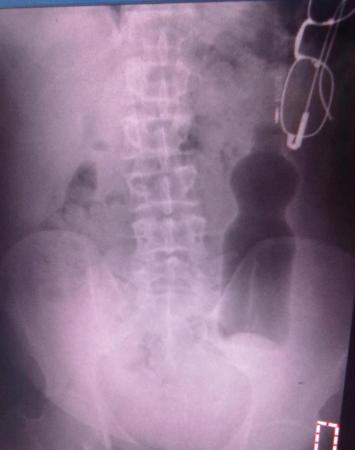

theCio Mesaj tarihi: Temmuz 13, 2011 Mesaj tarihi: Temmuz 13, 2011 Ahahaha bırak allah aşkına :D Düşünce makatına pet şişe girdi Edirne'de duş yapmak için girdiği banyoda ayağı kayınca pet şişenin üzerine düştüğünü söyleyen 50 yaşındaki adam yakınları tarafından hastaneye kaldırıldı. Makattan girerek ince bağırsaklara kadar ulaşan 330 mililitrelik pet şişe, ameliyatla çıkarıldı. Edirne’de oturan 50 yaşındaki erkek, iddialara göre duş yapmak için banyoya girdi.Üzerindeki kıyafetleri çıkardığı sırada dengesini kaybettiği belirtilen vatandaş düştü ve o sırada yerde bulunan 330 mililitrelik pet şişenin üzerine oturdu. Acı içinde kıvranan vatandaşın çığlıkları üzerine banyoya gelen yakınları, hemen Trakya Üniversitesi Tıp Fakültesi acil servisine getirildi. Burada gömlek cebinde kalan gözlüğü ile birlikte röntgen filmi çekilen adamın üzerine düştüğünü iddia ettiği pet şişenin ince bağırsaklara kadar ulaştığı ve o bölgedeki kolonlarda kaldığı görüldü. Genel Cerrahi servisinde ameliyata alınan vatandaşın makatından girdiği tespit edilen pet şişe, yapılan operasyonun ardından karnı kesilerek ameliyatla çıkarıldı. 1 gün hastanede müşade altında tutulan vatandaş, daha sonra hastaneden taburcu edildi. http://gundem.milliyet.com.tr/dusunce-makatina-pet-sise-girdi/gundem/gundemdetay/13.07.2011/1413885/default.htm.com